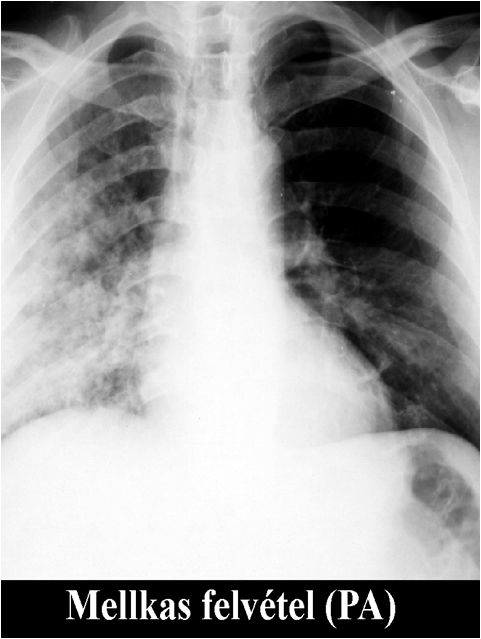

Figure 1.: The same picture in the same size, but with different resolution (a) 128x128 pixel and (b) 512x512 pixel.

Every pixel is a sample from the original image. If more samples are taken, the larger the number and the lesser the size of the pixels are, resulting in a higher resolution and accuracy.